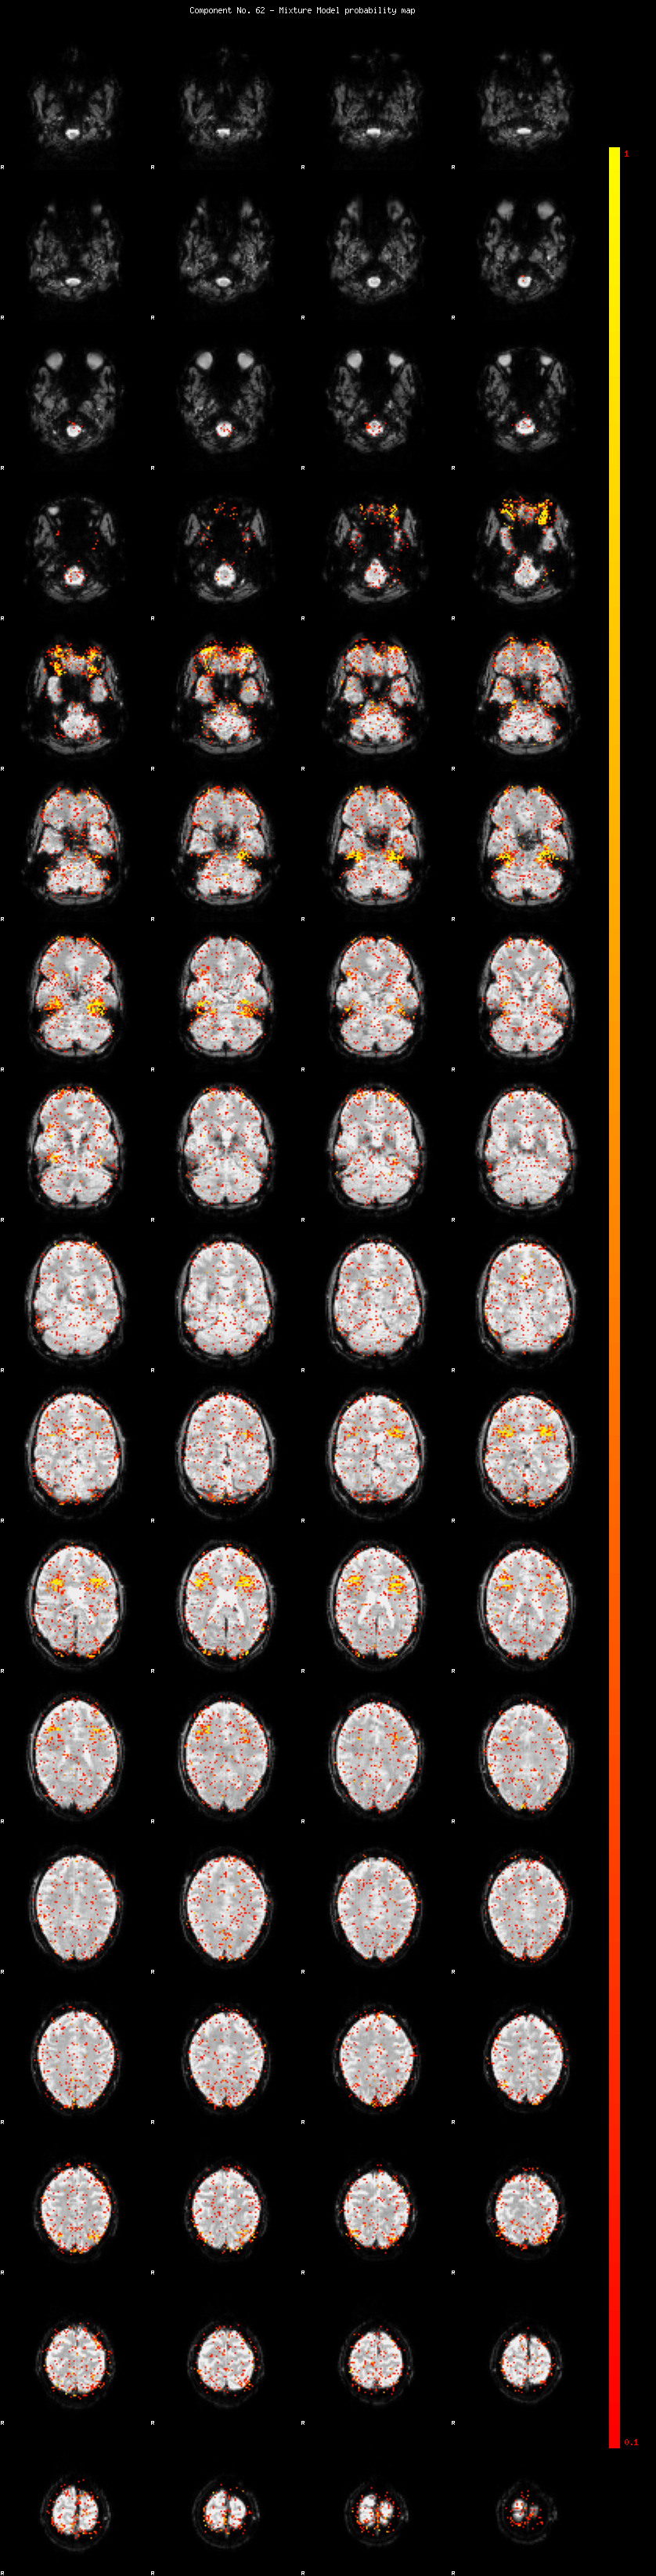

IC_62 Mixture Model fit

Means : -0.000000 2.322724 -2.457706

Vars : 1.000000 1.572782 1.980694

Prop. : 0.951940 0.022723 0.025337